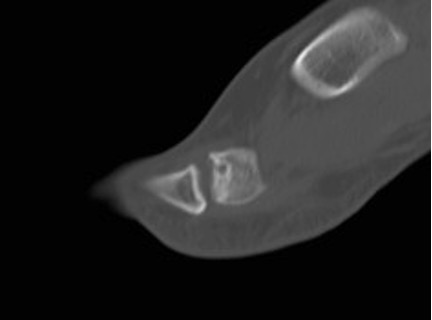

CT can help define the morphology of the MT head, especially when planning osteotomies (Figure 4).

Figure 4: sagittal CT slice through the 2nd MTPJ showing the relative involvement of the dorsum of the head; this illustrates how a dorsal wedge resection osteotomy would rotate articular surface into contact with the base of the proximal phalanx